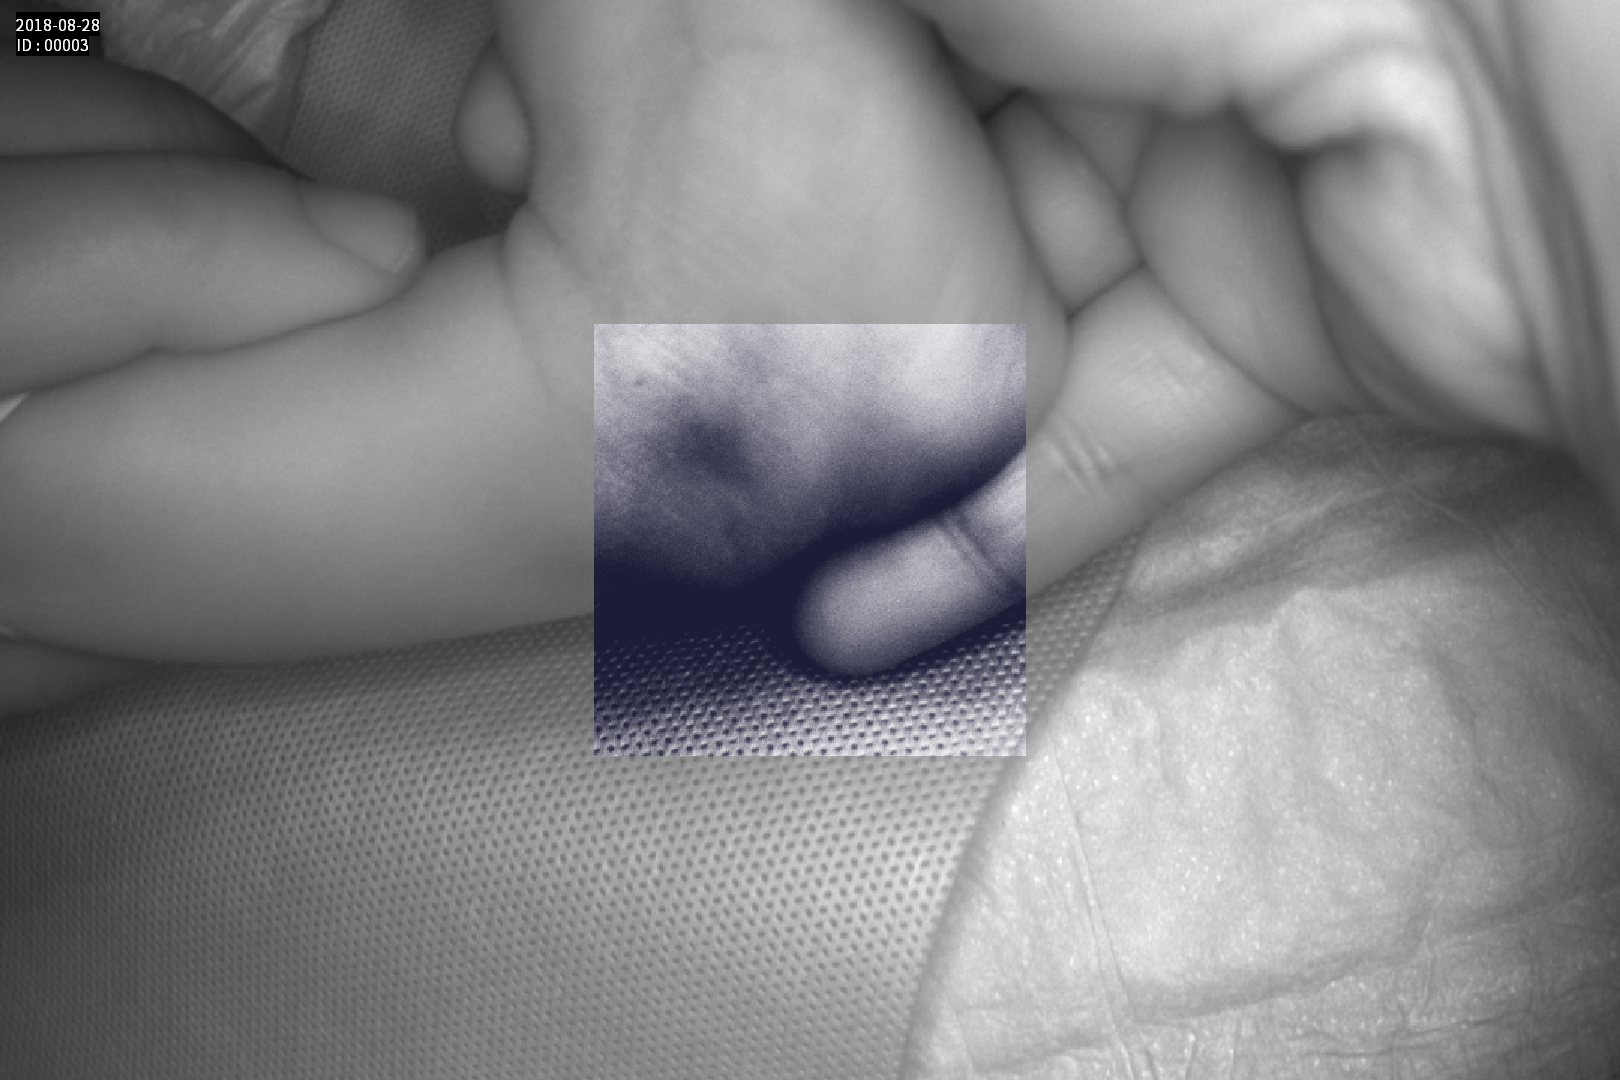

Dispozitiv medical portabil, non-contact, ce ajută la vizualizarea venelor pentru efectuarea puncției venoase, intervențiilor chirurgicale plastice, diagnosticul venelor varicoase.

Imaginea venelor este proiectată pe monitorul propriu în timp real si ajută la identificarea corectă și precisă

- Camera de vizualizare cu tehnologie infrarosu